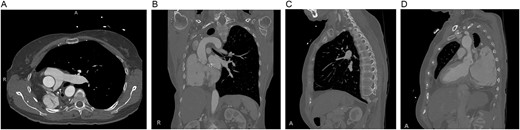

Mild–moderate TR was first noted on transthoracic echocardiogram 5 years after pneumonectomy and continually worsened over the next 10 years until she had wide open severe TR with moderate RV dilation and moderate global reduction in RV function. After multidisciplinary evaluation, TVR was recommended. Preoperative imaging revealed notable mediastinal shift to the right, severe counterclockwise rotation and displacement of the heart to the right and expansion of the left lung into the right hemithorax (Figs 1 and 2).

Preoperative computed tomography of the chest. Axial (A), coronal (B) and sagittal (C, D) views demonstrating displacement of the heart and left lung into the right hemithorax.